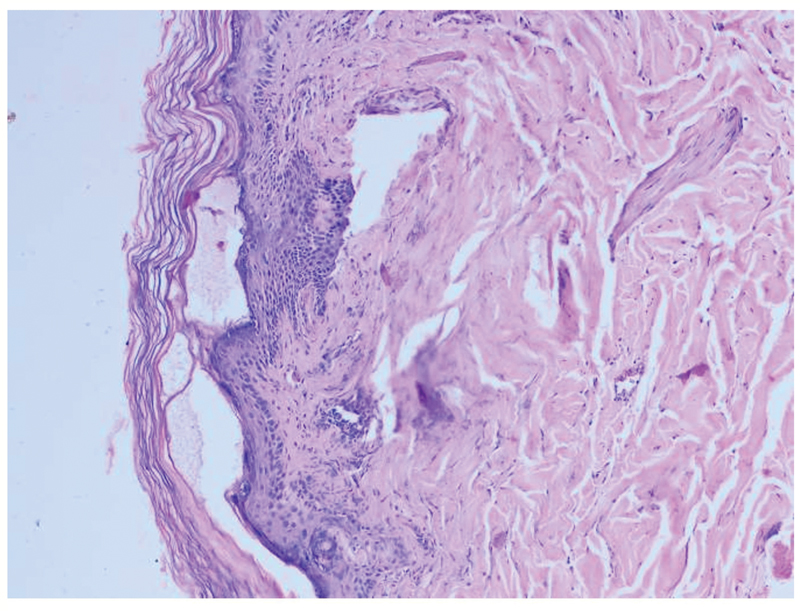

Punch biopsy taken from the lesions on the left forearm and left medial foot, on hematoxylin-eosin-stained specimen, light microscopy features suggested TEN ([Fig. 2]). Diagnosis of docetaxel-induced TEN was confirmed and managed with intravenous fluids, vasopressors, steroids, antibiotics, and total parenteral nutrition with hypothermia prevention. Secondary infection control and skin care were instituted. Unfortunately, patient died on the sixth day of hospitalization.

| Fig. 2 Biopsy images and pathology report: microscopic examination of the skin (hematoxylin and eosin stain) was performed. The punch biopsies from the edges of both lesions (left forearm and left medial foot) show similar morphologic features (1) orthokeratosis of epidermis, (2) follicular plugging, (3) subcorneal separation and small vesicle formation, (4) basal vacuolar changes, (5) superficial dermis shows perivascular lymphoplasmacytic infiltrate, (6) papillary dermis shows mild edematous changes, and (7) interstitium shows increased mast cells. The histologic features are consistent with toxic epidermal necrolysis/Stevens–Johnson's syndrome.